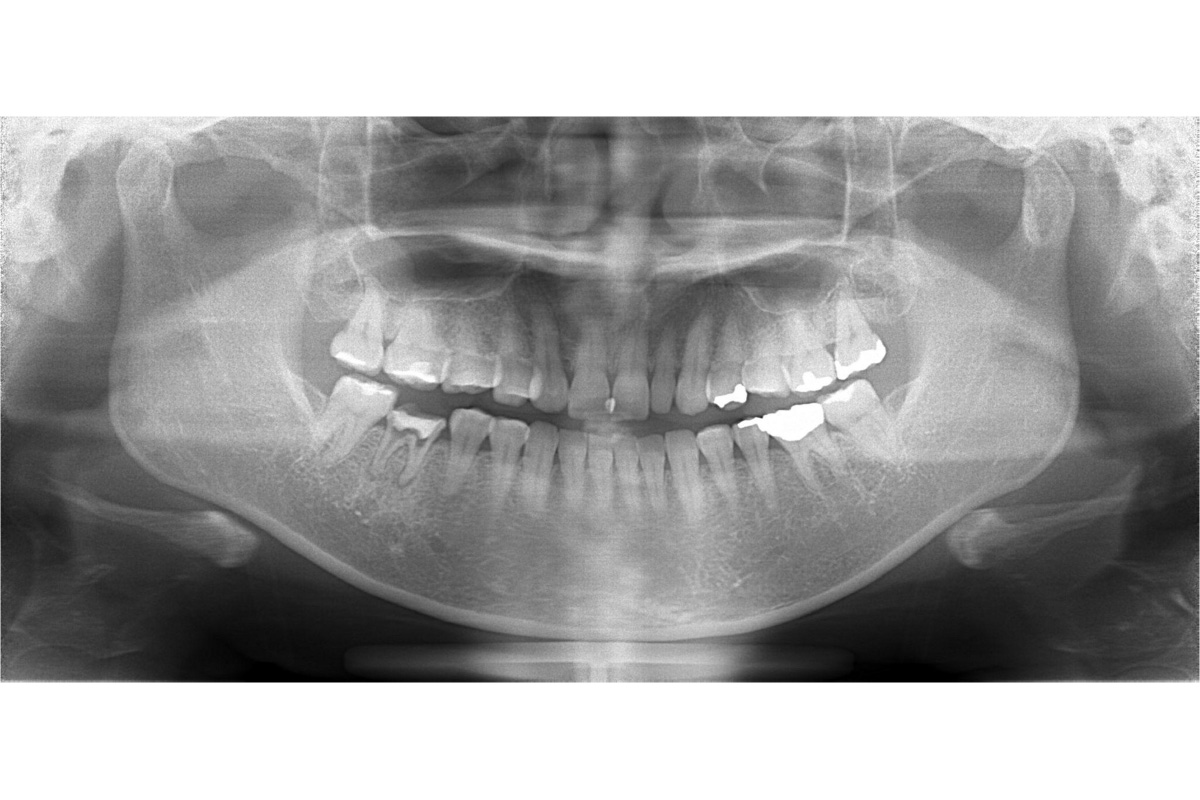

治療前